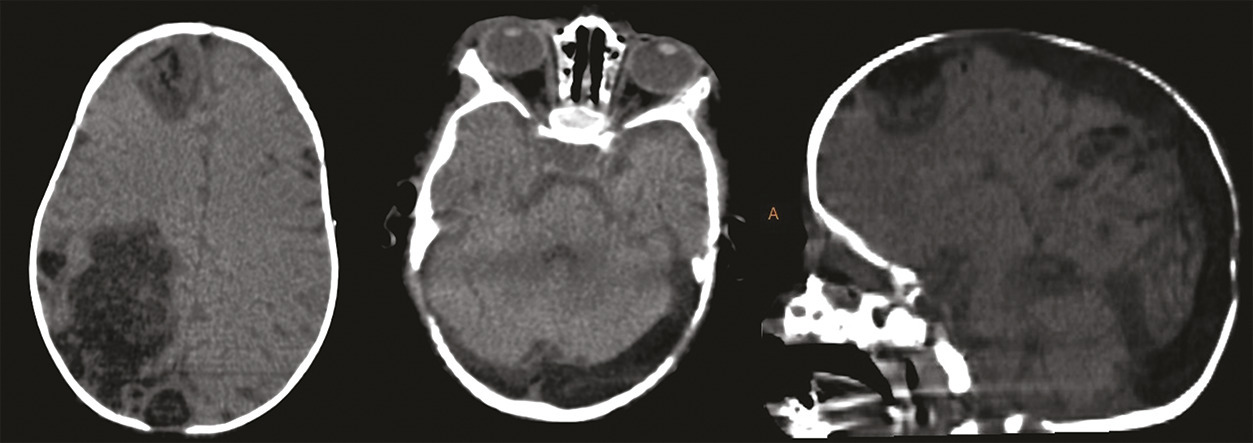

Ce nourrisson de 5 mois était admis aux urgences pour une crise convulsive généralisée. Issu d’un mariage consanguin, il était né par voie basse, sans notion de souffrance néonatale ni antécédents pathologiques notables. L’examen clinique trouvait un syndrome méningé fébrile. Un bilan biologique, une ponction lombaire, une tomodensitométrie et une imagerie par résonance magnétique cérébrales (fig. 1 et 2) étaient réalisés en urgence. Les prélèvements sanguins et du liquide céphalorachidien avaient un aspect lactescent, en faveur d’une méningite bactérienne, et le bilan lipidique était très perturbé : hypercholestérolémie totale à 17 g/L avec un LDL-cholestérol très élevé et un HDL-cholestérol très bas. L’imagerie montrait des plages lésionnelles parenchymateuses cérébrales droites, frontale et pariétale, de signal graisseux et une thrombophlébite cérébrale des sinus longitudinal et latéraux ainsi que quelques veines corticales de signal graisseux. Le diagnostic d’hypercholestérolémie primaire était posé. Le nourrisson était hospitalisé en réanimation et mis sous régime hypolipidémiant.